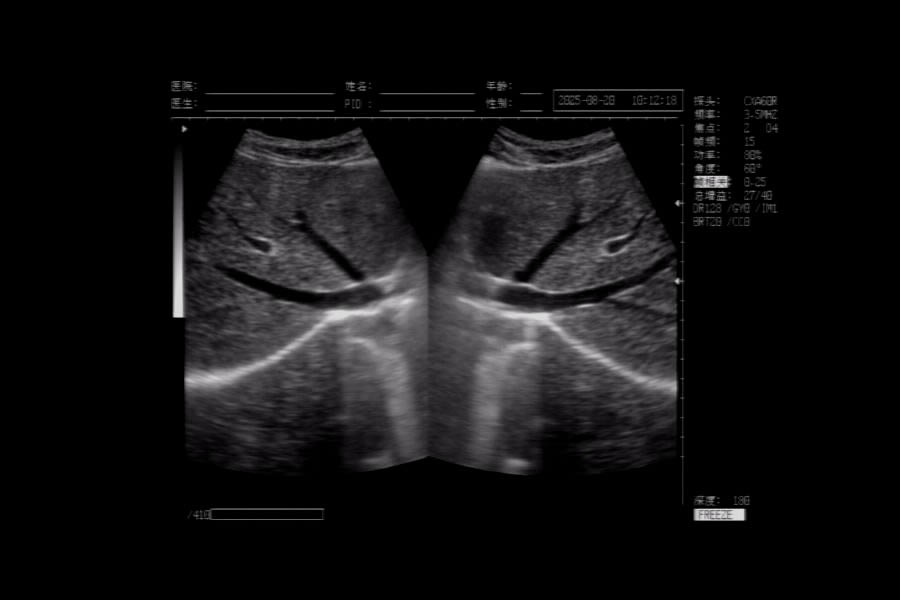

一般的B超檢測(cè),以檢查腹部臟器為主,如肝臟、膽囊、胰腺、脾臟和腎臟等。另外,乳腺、甲狀腺、前列腺和婦科檢查,也可使用B超。不同部位的B超,需要注意的事項(xiàng)不一樣。